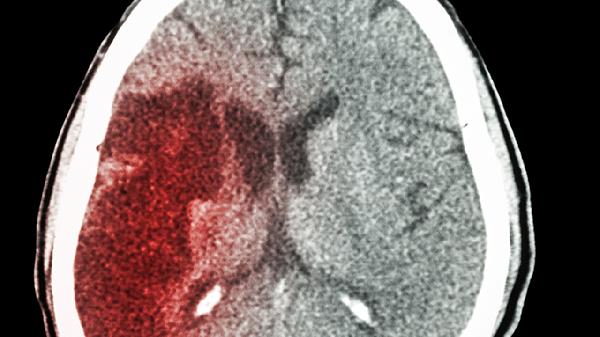

脑出血和脑梗塞的预后恢复情况通常与病情严重程度、治疗时机等因素有关,多数情况下脑梗塞的神经功能恢复概率高于脑出血,但脑出血的急性期死亡率更高。

脑出血患者因血肿对脑组织的直接破坏和继发性脑水肿,往往造成不可逆损伤。即便血肿吸收后,原出血区域的神经功能恢复难度较大。脑室出血或出血量超过30毫升的患者预后较差,常伴随认知障碍、运动功能障碍等长期后遗症。但小量出血且未累及关键功能区的患者,经过积极治疗也可能获得较好恢复。